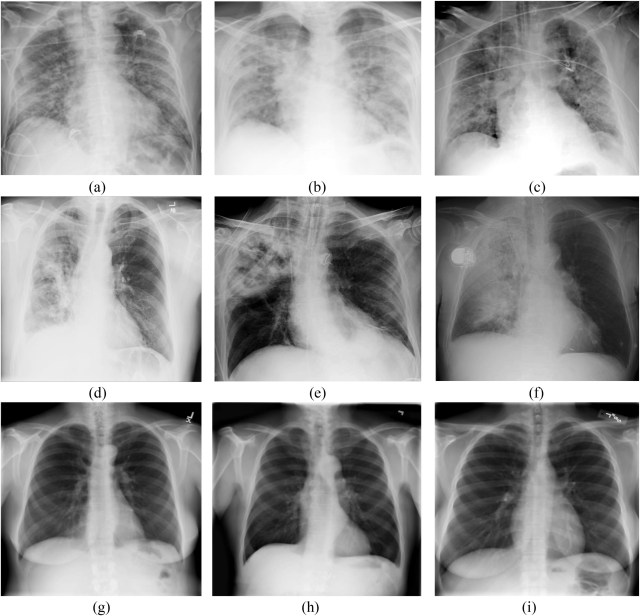

Ground-glass-opacity is not pneumonia, though most commonly that term is used for simplicity. Ground-glass-opacity is like a bathroom window, which is deliberately made to high opacity to prevent seeing through it. So ground-glass-opacity means it is an area of the lung that has “something” that cannot be seen. This article shows a wonderful image that compares 3 images with ground-glass-opacity lungs with 3 images with pneumonia and 3 images with normal lungs. So you can see the differences. The top 3 are ground-glass-opacity, the middle 3 are pneumonia, and the bottom 3 are healthy normal lungs.